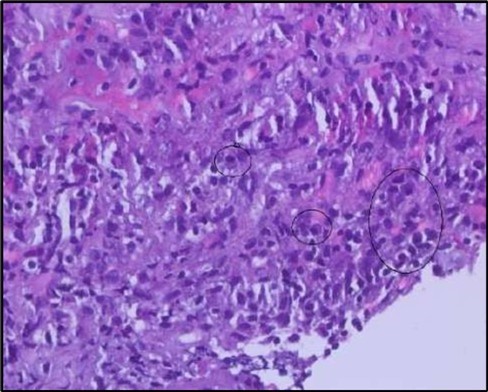

Figure 5b.OS, High-power H&E view showing dense inflammatory infiltration within the corneal stroma composed predominantly of lymphocytes and numerous plasma cells (circles highlight plasma cells).

Histopathological examination revealed a dense infiltration of CD138-positive plasma cells within the excised conjunctival tissue (Figure 5b, Figure 5c, Figure 5d). This finding supports an antibody-mediated immunopathogenesis in Mooren’s ulcer, consistent with Type II and Type III hypersensitivity mechanisms described in the literature 20, 21. The prominent presence of CD138- positive plasma cells provide a clear pathological rationale for conjunctival resection, as excision of the immunologically active perilimbal conjunctiva effectively removes the local 'factory' of autoantibodies that drive corneal stromal destruction, thereby halting ongoing tissue damage 21.